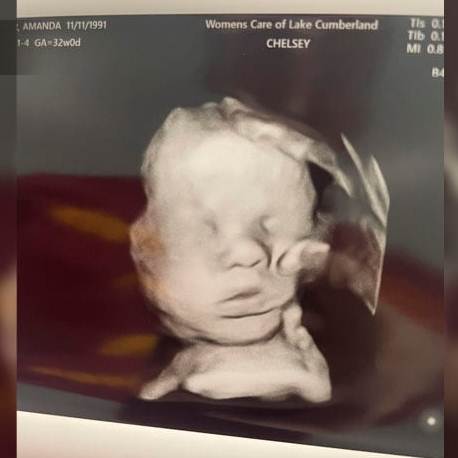

Amanda Foster, una mujer de Kentucky, Estados Unidos, compartió en Facebook una ecografía que ha conmovido a miles: en la imagen, aparece lo que parece ser una mano sosteniendo la cabeza de su hijo por nacer, y es que Amanda asegura que es “la mano de Dios”.

La joven madre explicó que su hija menor, Bailey, fue la primera en notar la figura en la ecografía, preguntando: “¿De quién es esa mano?”. Esta observación impulsó a Amanda a ver el detalle que para ella representa una señal del cielo.

Amanda tiene la costumbre de orar antes de cada consulta médica, pidiendo: “por favor, mantén tu mano en mi bebé”. Al ver la imagen de la mano, sintió que Dios había respondido a su oración y estaba cuidando a su pequeño desde el vientre.

Aunque sus dos embarazos siguientes fueron sin complicaciones, el actual presenta un defecto cardíaco congénito. Sin embargo, Amanda mantiene la esperanza y recibe la imagen como “un mensaje de Dios” que le trae paz.

La foto ha causado impacto en redes sociales, generando comentarios de aliento, oraciones y testimonios similares de fe entre los usuarios. Aunque no hay confirmación científica de que sea una mano, para Amanda es un recordatorio de las promesas de Dios.